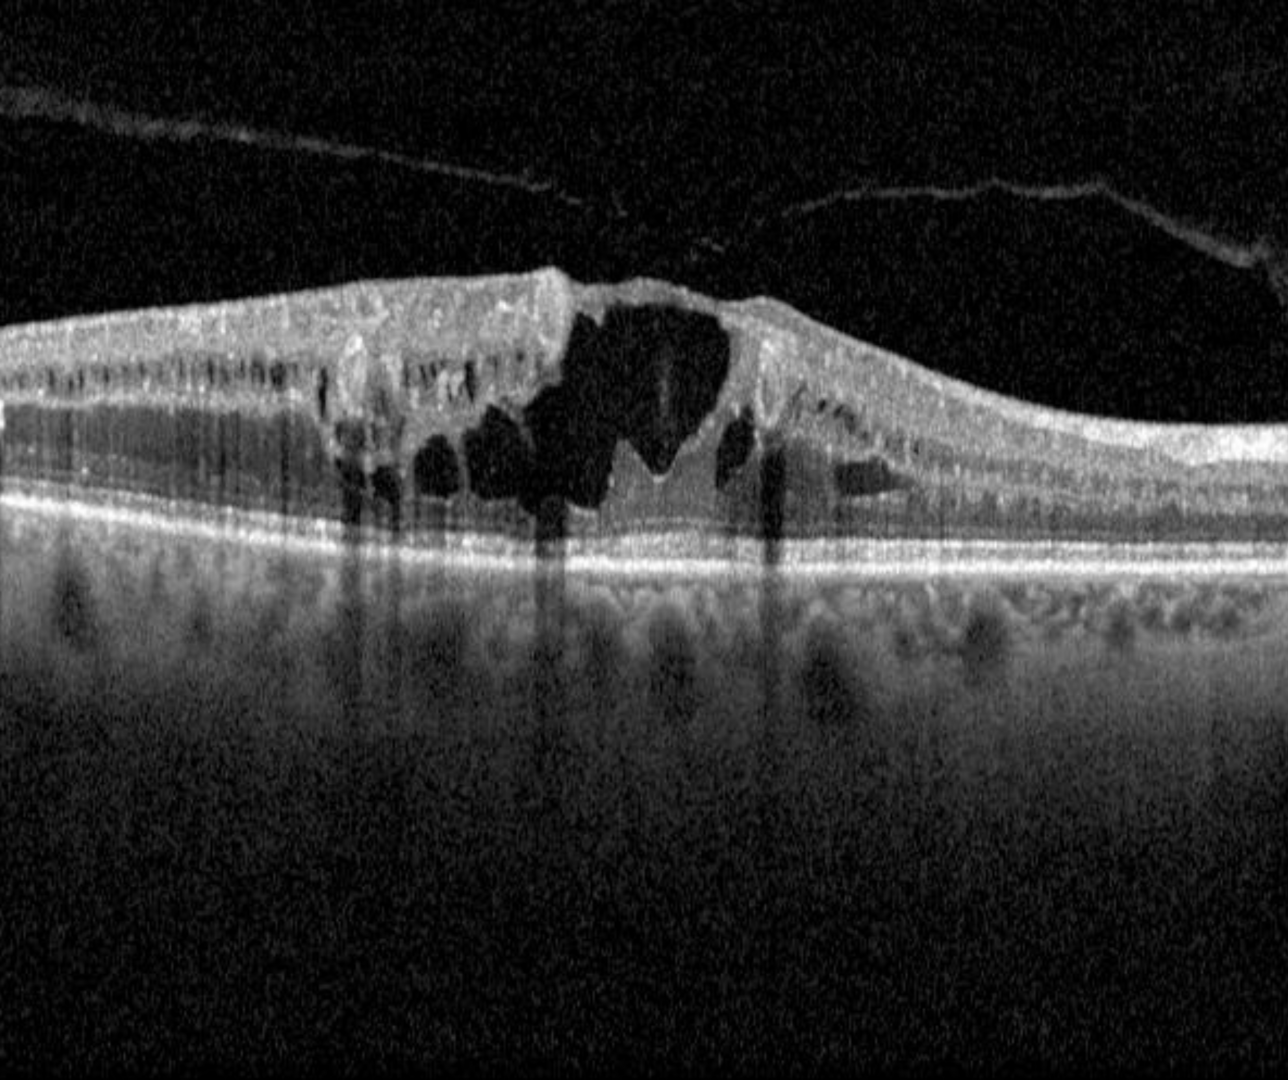

Signs of macular oedema may include both hard exudates (discrete, yellow-white lipid deposits) and retinal thickening or cystic spaces within either the inner and outer retinal layers. More advanced cases may present with subretinal oedema. For more information on each of these, please refer to the page "Diabetic retinopathy overview" - available using the link at the bottom of this page.

It is important to note that these two signs can exist independently of each other. If only hard exudates are present (no retinal thickening or cystic spaces), this indicates previous macular oedema. The presence of cystic spaces indicates current oedema, whether or not hard exudates are also present. For this reason, OCT is now considered an important part of a diabetic examination when diabetic macular oedema is suspected, however it should also be noted that diffuse retinal oedema may be difficult to detect on OCT imaging.

Case 1: Centre-involving diabetic macular oedema

A 65-year-old Asian male who was diagnosed with type 2 diabetes 10 years previous. He is unsure of his latest HbA1c. His best corrected visual acuity in the right eye is 6/12-1 (20/40-1). This case will focus on the right eye only.